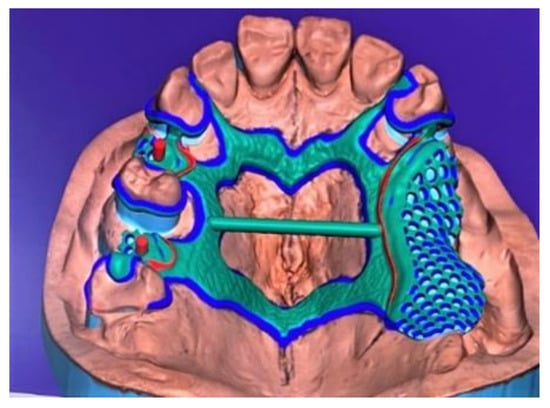

In the hybrid procedure, the second analog model was scanned using a laboratory scanner (Neway Open Tech 3D) to create the correspondent digital model, then the CAD modeling of the removable partial denture (RPD) was realized (Figure 14). The selective laser melting machine was then connected to the computer to realize the skeleton structure through the application and the melting of hundreds of chrome–cobalt dust layers (Figure 15). The structure was finalized by applying some aesthetic clasps made of nylon (Figure 16).

Figure 14. CAD modeling of the framework.